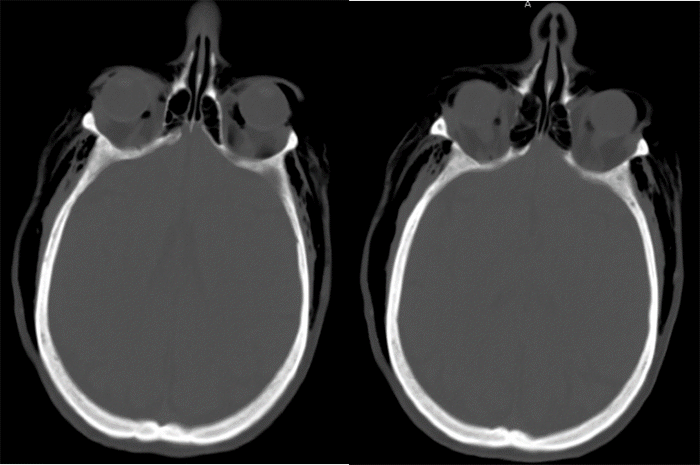

A 58-year-old male presented as a Level I trauma status post fall at home. Per history, the patient fell from a standing height and struck his right chest wall on a table mid-fall. He awoke the next morning with facial edema, prompting the call to EMS. He was initially evaluated at an outside facility and found to have pneumomediastinum, diffuse subcutaneous emphysema, and a right pneumothorax. His subcutaneous emphysema worsened after endotracheal intubation and a right-sided chest tube was placed before transfer. CXR on admission showed a right lateral 4th rib fracture with possible additional rib fractures. Various imaging was obtained after arrival, including CT of the head, cervical, thoracic, and lumbar spine, and CTA of the neck, chest, abdomen, and pelvis. These studies were remarkable for extensive subcutaneous emphysema in the bilateral neck, chest, abdomen, pelvis, and subconjunctival emphysema (Figure 1).

Figure 1. CT Head Scan Demonstrating Subconjunctival Emphysema Bilaterally. Published with Permission